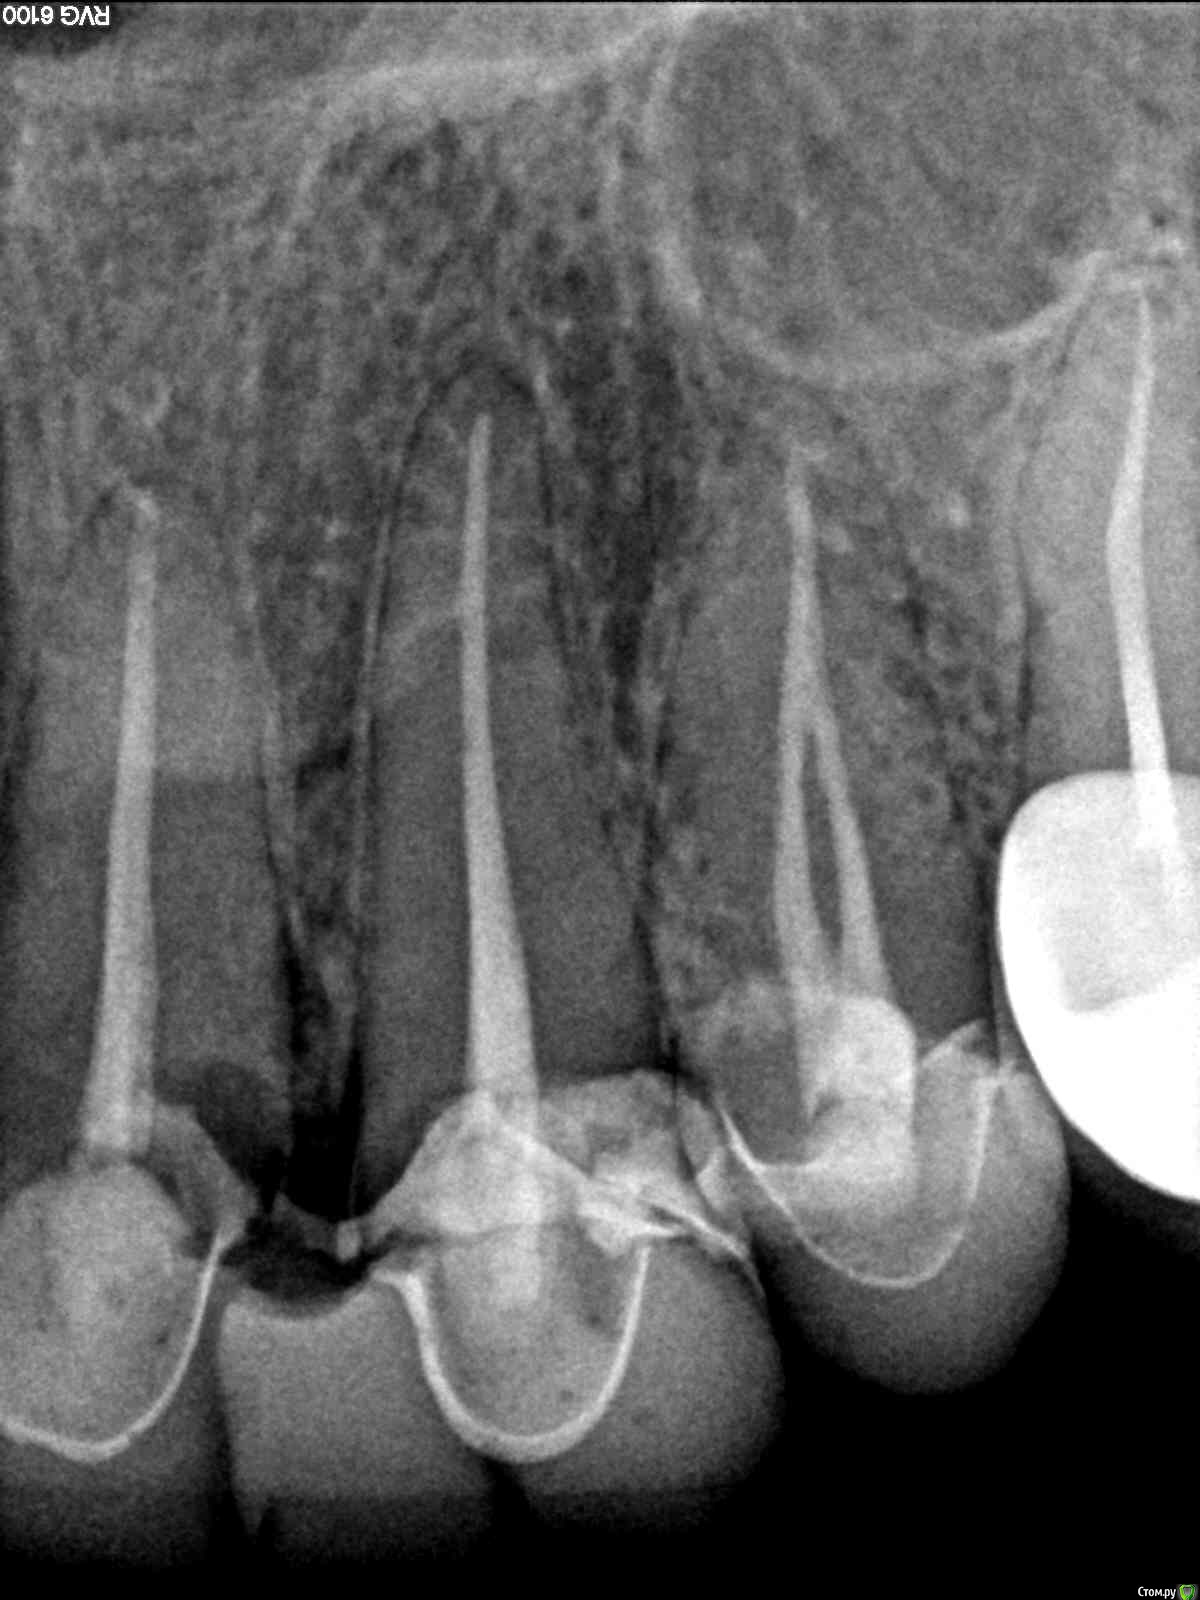

lazzal Опубликовано 30 октября, 2015 Автор Поделиться Опубликовано 30 октября, 2015 Посмотрите пожалуйста в каком состоянии зуб под коронкой, возможно ли его спасти? Ссылка на комментарий

Bier Опубликовано 30 октября, 2015 Поделиться Опубликовано 30 октября, 2015 В плачевном состоянии, его сохранение под вопросом 1 Ссылка на комментарий